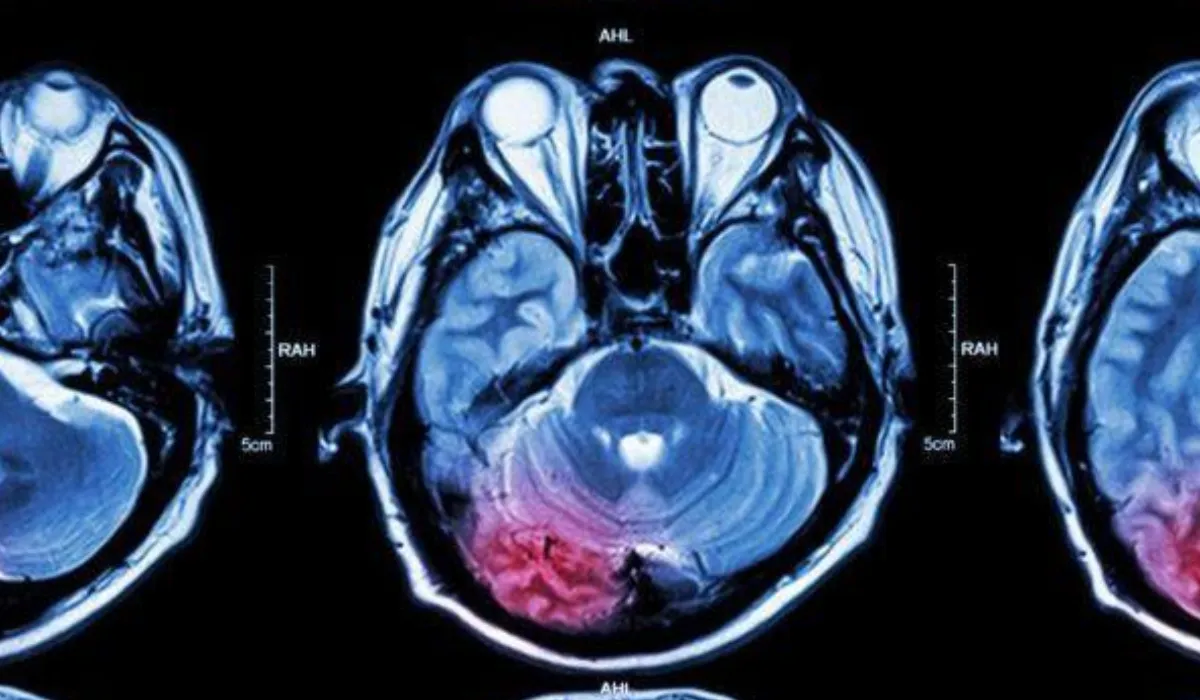

El análisis de sangre para detectar tumores cerebrales representa un avance prometedor que podría cambiar la forma en que se detectan y monitorean estas enfermedades.

Un equipo de científicos liderado por la Universidad de Manchester, en colaboración con investigadores de Dinamarca, desarrolló una prueba capaz de identificar tumores cerebrales con una precisión superior al 90 por ciento. El estudio se publicó en la revista Neuro-oncology Advances.

Actualmente, el diagnóstico de estos padecimientos suele implicar procedimientos invasivos como biopsias o múltiples resonancias magnéticas. Este nuevo enfoque propone una alternativa más rápida y menos agresiva para los pacientes.